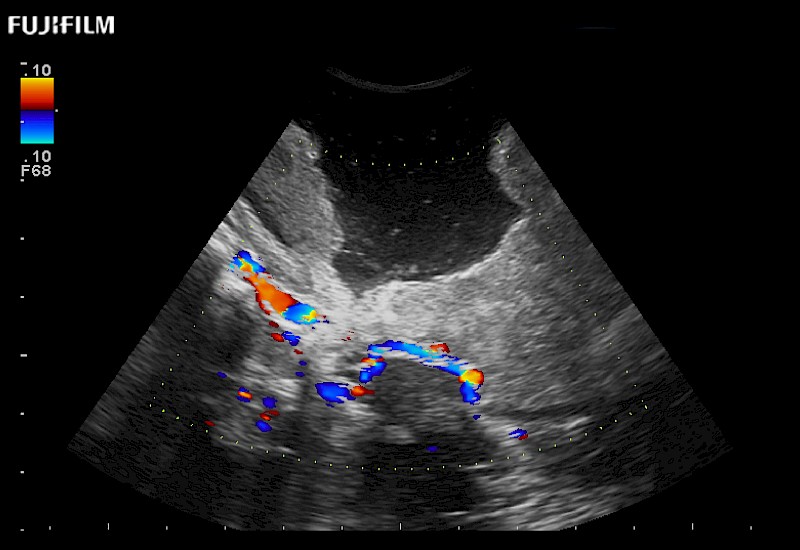

Exclusive 10mm side‐fire linear array transducer with 2.87mm diameter is ideal for real‐time visualization through and behind structures and instant, scalable definition of anatomy and vascularity including the ability to delineate and define tumor margins.

Main Specifications: